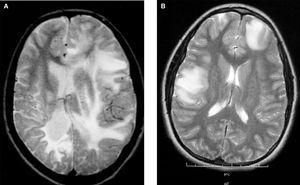

2.Afectación multifocal con lesiones hiperintensas en T2 ponderada o FLAIR (fluid-attenuated inversion recovery) en la RM craneal o medular indicativas de desmielinización (fig. 1).

Figura 1.Cortes transversales de RM cerebral en T2 con áreas de hiperseñal indicativas de lesiones desmielinizantes.A)Afectación bihemisférica de la sustancia blanca de predominio derecho con áreas de afectación cortical en dicho hemisferio. B)Lesiones globulosas corticosubcorticales frontal derecha y temporoparietal izquierda.